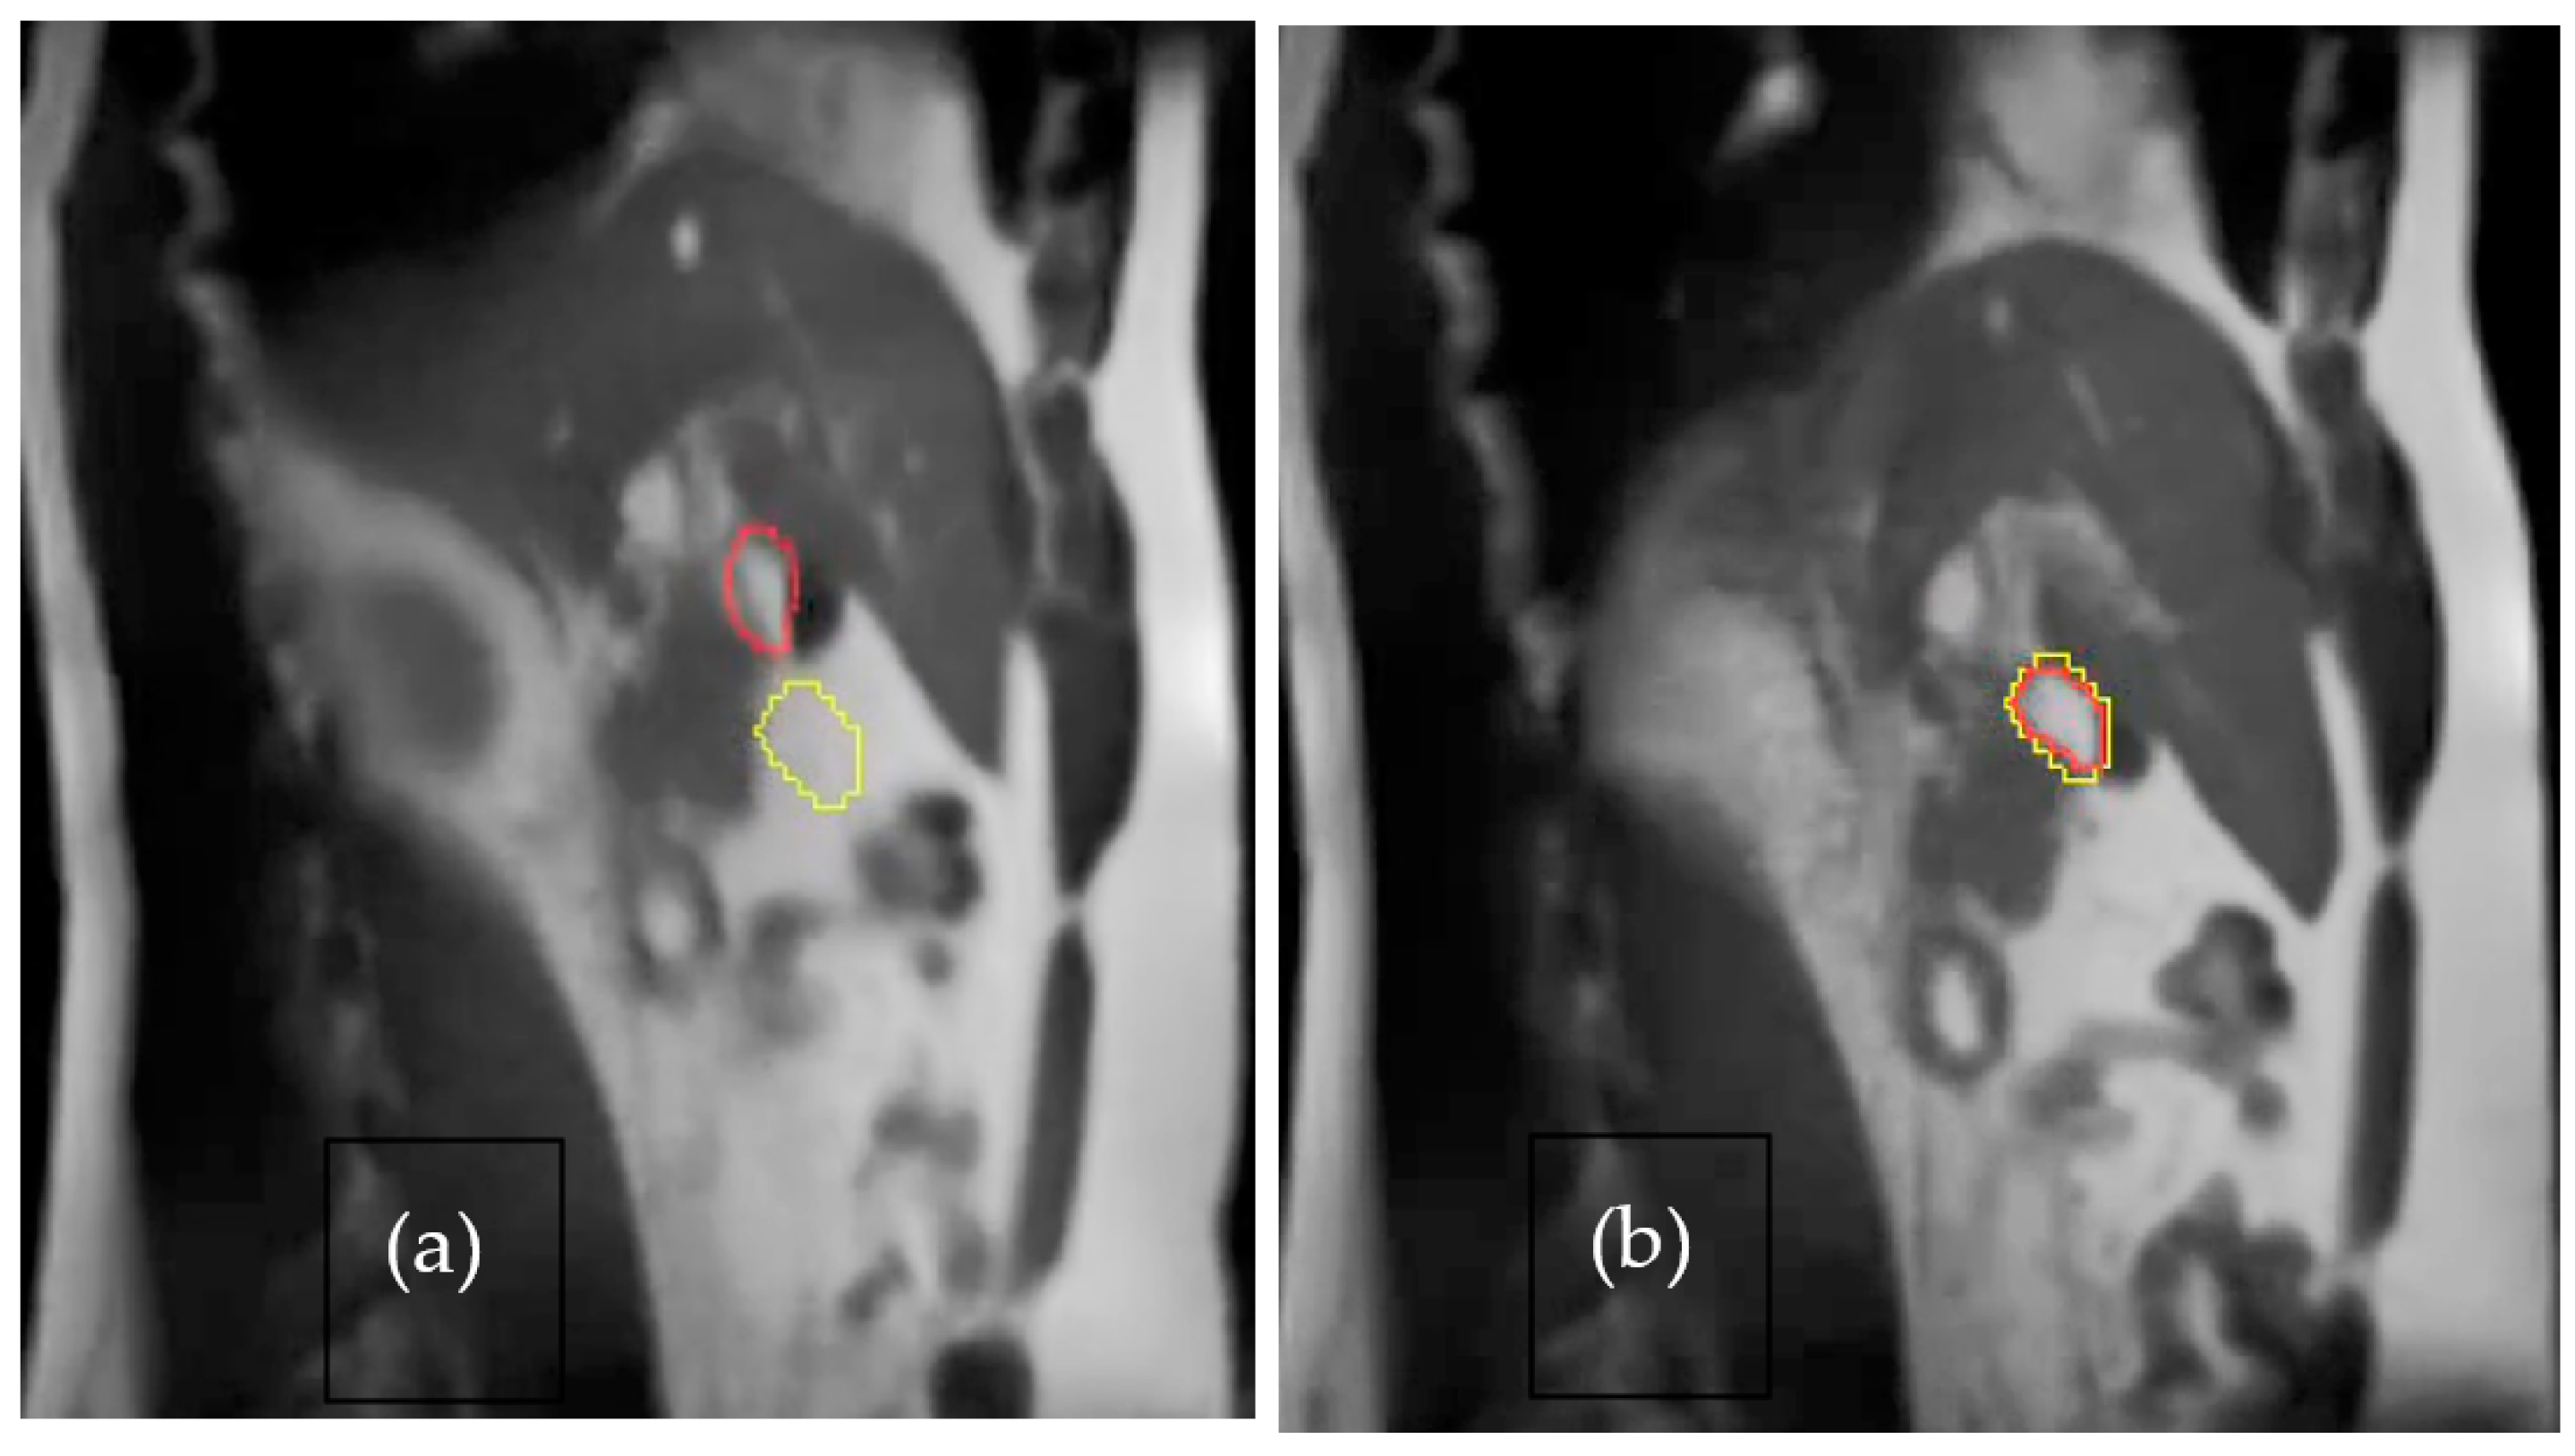

- Das, I.J.; McGee, K.P.; Tyagi, N.; Wang, H. Role and future of MRI in radiation oncology. Br. J. Radiol. 2019, 92, 20180505. [Google Scholar] [CrossRef]

- Chandarana, H.; Wang, H.; Tijssen, R.H.N.; Das, I.J. Emerging Role of MRI in Radiation Therapy. J. Magn. Reson. Imaging 2018, 48, 1468–1478. [Google Scholar] [CrossRef] [PubMed]